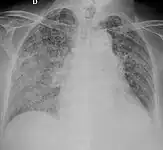

X-ray, showing extensive bilateral reticulo-nodular infiltrates -